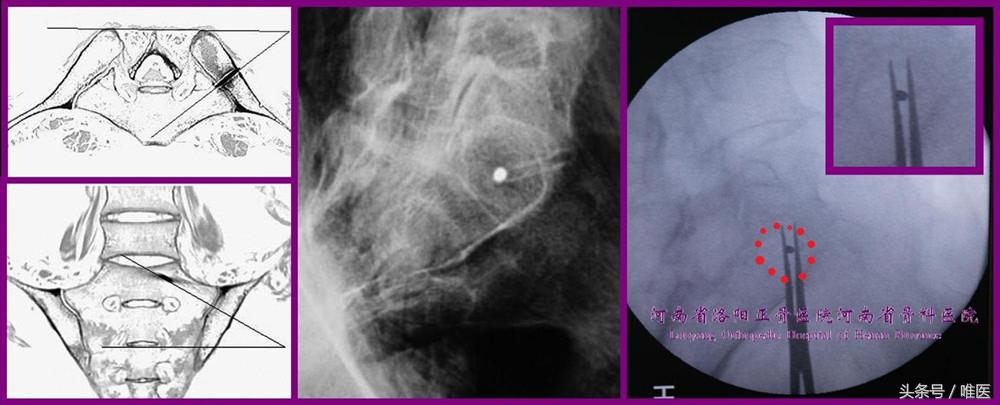

3. 骶骨侧块轴位像(图7)

方法:沿骶1椎体侧块的轴进行X线投射,即病人俯卧以骶1椎体侧块为中心,X线由尾端、后部、外侧向头端、前部、内侧投射(具体角度需进行CT测量)所得到的图像。

内容:此像上可出现一个由SAS与骶神经根管前缘线所围成的椭圆形的置钉安全区域。

意义:此椭圆形区域可确定骶髂螺钉的进钉点。与上述“非标准骶骨侧位像”相比,此图像所需射线的复合投射角度较大,进钉点区域极靠后而接近髂后上棘,在病人仰卧位的情况下实难进行置钉操作,强烈建议在俯卧位下进行。

图7. 骶骨侧块轴位像的成像方法及其所显示的椭圆形螺钉安全通道(红)及进钉点(前两列图片引自参考文献15)。

4. 骨盆出口位像(图8)

方法:自骨盆正位像,在矢状面上调整X线投射角度,使得耻骨联合与骶正中嵴重叠且双侧耻骨结节与骶2椎体重叠(置入骶1骶髂螺钉时)或双侧耻骨结节与骶3椎体重叠(置入骶2骶髂螺钉时)。

内容:此像可很好地显示骶1、骶2骶前孔及“八”字形神经根管的外缘、骶1椎体的上终板、骶1/2残存的椎间盘等。

意义:确定骶髂螺钉在骶1、骶2椎体及侧块内的走向,避免螺钉进入骶前孔内或突入腰5/骶1椎间隙内。

图8. 骨盆出口位像所示骶髂螺钉与骶前孔等重要结构间的位置关系。